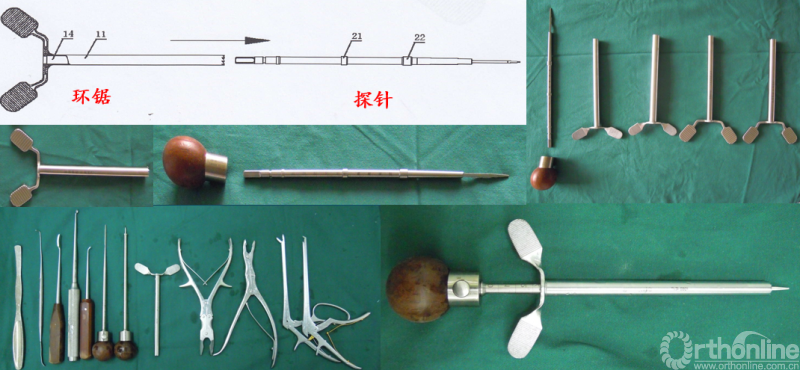

核心技术展示

创新环钻展示

其团队在椎间盘退变形成因素的相关研究中发现,椎间盘退变与凋亡有关,因而临床上使用雌激素可缓解椎间盘退变。此外,改良PSO—“环钻经椎弓根椎体截骨”,与传统截骨工具相比,“环钻”优势为安全性高,环钻侧壁光滑,且无需持续牵拉硬膜;稳定性好,顶端为波浪锯齿状,与骨接触紧密;截骨效率高,取骨量大、可调整方向多角度截骨。